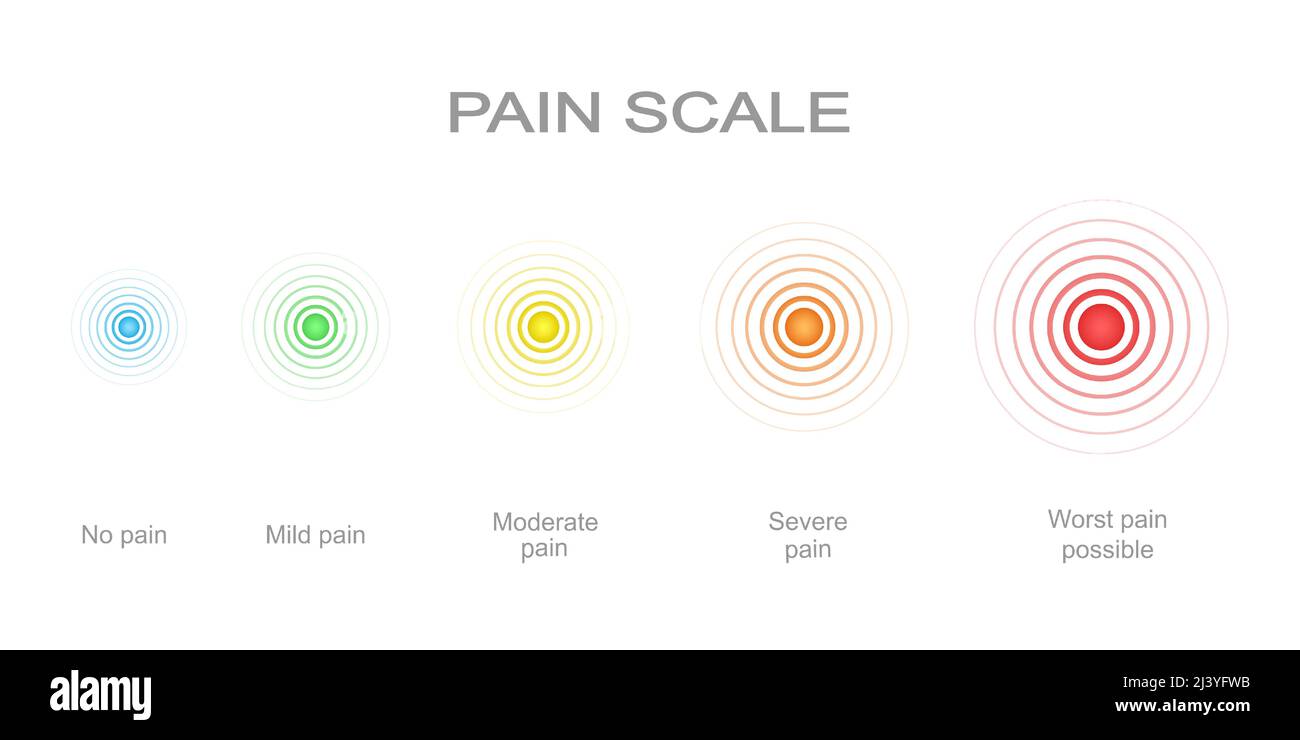

Schmerzmessskala mit mehrfarbigen Schmerzpunkten. Verletzte Messwertstände mit konzentrischen Anzeichen für die Lokalisierung von Schmerzen. Medizinisches Kommunikationstool für das Screening von Patientenerkrankungen. Vektorgrafik Stock Vektorhttps://www.alamy.de/image-license-details/?v=1https://www.alamy.de/schmerzmessskala-mit-mehrfarbigen-schmerzpunkten-verletzte-messwertstande-mit-konzentrischen-anzeichen-fur-die-lokalisierung-von-schmerzen-medizinisches-kommunikationstool-fur-das-screening-von-patientenerkrankungen-vektorgrafik-image464195801.html

Schmerzmessskala mit mehrfarbigen Schmerzpunkten. Verletzte Messwertstände mit konzentrischen Anzeichen für die Lokalisierung von Schmerzen. Medizinisches Kommunikationstool für das Screening von Patientenerkrankungen. Vektorgrafik Stock Vektorhttps://www.alamy.de/image-license-details/?v=1https://www.alamy.de/schmerzmessskala-mit-mehrfarbigen-schmerzpunkten-verletzte-messwertstande-mit-konzentrischen-anzeichen-fur-die-lokalisierung-von-schmerzen-medizinisches-kommunikationstool-fur-das-screening-von-patientenerkrankungen-vektorgrafik-image464195801.htmlRF2HY5XDD–Schmerzmessskala mit mehrfarbigen Schmerzpunkten. Verletzte Messwertstände mit konzentrischen Anzeichen für die Lokalisierung von Schmerzen. Medizinisches Kommunikationstool für das Screening von Patientenerkrankungen. Vektorgrafik

Schmerzskala mit konzentrischen Schmerzpunkten von blau bis rot. Verletzte Meterwerte mit mehrfarbigen Lokalisierungszeichen der Schmerzen. Medizinisches Tool für das Screening von Patientenerkrankungen. Vektorgrafik Cartoon-Illustration Stock Vektorhttps://www.alamy.de/image-license-details/?v=1https://www.alamy.de/schmerzskala-mit-konzentrischen-schmerzpunkten-von-blau-bis-rot-verletzte-meterwerte-mit-mehrfarbigen-lokalisierungszeichen-der-schmerzen-medizinisches-tool-fur-das-screening-von-patientenerkrankungen-vektorgrafik-cartoon-illustration-image467129079.html

Schmerzskala mit konzentrischen Schmerzpunkten von blau bis rot. Verletzte Meterwerte mit mehrfarbigen Lokalisierungszeichen der Schmerzen. Medizinisches Tool für das Screening von Patientenerkrankungen. Vektorgrafik Cartoon-Illustration Stock Vektorhttps://www.alamy.de/image-license-details/?v=1https://www.alamy.de/schmerzskala-mit-konzentrischen-schmerzpunkten-von-blau-bis-rot-verletzte-meterwerte-mit-mehrfarbigen-lokalisierungszeichen-der-schmerzen-medizinisches-tool-fur-das-screening-von-patientenerkrankungen-vektorgrafik-cartoon-illustration-image467129079.htmlRF2J3YFWB–Schmerzskala mit konzentrischen Schmerzpunkten von blau bis rot. Verletzte Meterwerte mit mehrfarbigen Lokalisierungszeichen der Schmerzen. Medizinisches Tool für das Screening von Patientenerkrankungen. Vektorgrafik Cartoon-Illustration

Vertikale Schmerzmessskala mit mehrfarbigen konzentrischen Kreisen. Verletzungen von Messwerten mit Schmerzen Lokalisierungspunkte Zeichen. Medizinisches Tool für das Screening von Patientenerkrankungen. Vektorgrafik Cartoon-Illustration Stock Vektorhttps://www.alamy.de/image-license-details/?v=1https://www.alamy.de/vertikale-schmerzmessskala-mit-mehrfarbigen-konzentrischen-kreisen-verletzungen-von-messwerten-mit-schmerzen-lokalisierungspunkte-zeichen-medizinisches-tool-fur-das-screening-von-patientenerkrankungen-vektorgrafik-cartoon-illustration-image465415889.html

Vertikale Schmerzmessskala mit mehrfarbigen konzentrischen Kreisen. Verletzungen von Messwerten mit Schmerzen Lokalisierungspunkte Zeichen. Medizinisches Tool für das Screening von Patientenerkrankungen. Vektorgrafik Cartoon-Illustration Stock Vektorhttps://www.alamy.de/image-license-details/?v=1https://www.alamy.de/vertikale-schmerzmessskala-mit-mehrfarbigen-konzentrischen-kreisen-verletzungen-von-messwerten-mit-schmerzen-lokalisierungspunkte-zeichen-medizinisches-tool-fur-das-screening-von-patientenerkrankungen-vektorgrafik-cartoon-illustration-image465415889.htmlRF2J15EM1–Vertikale Schmerzmessskala mit mehrfarbigen konzentrischen Kreisen. Verletzungen von Messwerten mit Schmerzen Lokalisierungspunkte Zeichen. Medizinisches Tool für das Screening von Patientenerkrankungen. Vektorgrafik Cartoon-Illustration